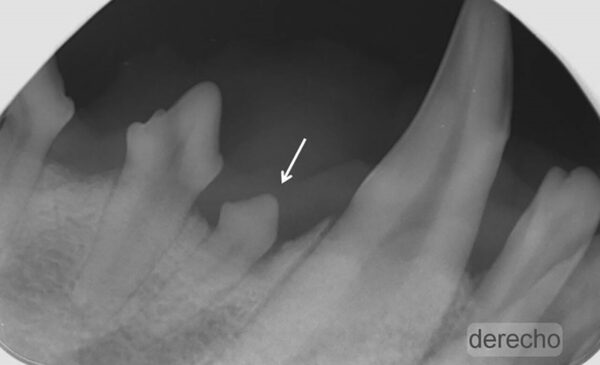

Alteración en el número y posición de los dientes

Ausencia dental

Cuando en una exploración visual de la boca observamos una ausencia dental debemos hacer una radiografía que nos indique la causa, que puede ser de origen genético o deberse a alteraciones sufridas durante las primeras etapas del desarrollo dental o a lo largo de la vida del animal.

A nivel radiológico nos podemos encontrar con varias situaciones:

- Ausencia del diente porque no se ha formado (agenesia).

- El diente no ha erupcionado por estar ectópico (fuera de su área anatómica).

- El diente está incluido o impactado (cuando no logra erupcionar o lo hace parcialmente por diferentes causas).

También puede ser debida a la pérdida dental (por EP, por ejemplo) o a fracturas de corona en las que quedan restos de estructuras dentales bajo la encía. Por tanto, dependiendo de ello, decidiremos el enfoque terapéutico que tomaremos en cada paciente con ausencia dental. (imágenes 14-17).